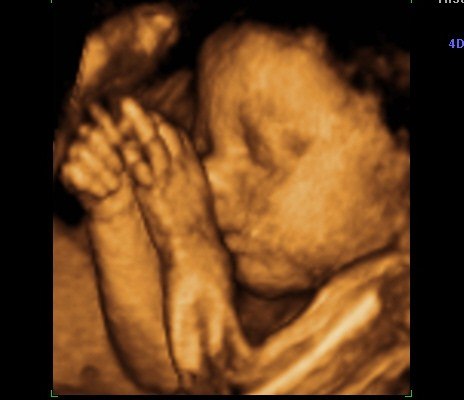

Efterfølgende er det bare blevet mere og mere omfattende for hver ny undersøgelse og scanning. I uge 10 var vi til genetisk rådgivning, da Mortens faster mangler hænder og fødder - det samme gør hendes datter. Allerede her var det lille hjerte blevet til en lille menneskefigur med boksehandsker ;o) I uge 12 var vi til NF-scanning og alt så godt ud. Igen så de efter hænder og fødder og alt var fint. Lav risiko for DS og fin baby. I uge 17 er vi til kønsscanning på en privatklinik og får at vide, at vi venter en lille pige. Fik set hende i 3D og tænk at der var sådan en fin lille en inden i min mave. Hun havde på dette tidspunkt ikke meget fedt på kroppen, så minder mest om en lille alien. Men hun er vores lille rumvæsen. I uge 19 er vi til MD-scanning og får at vide, at det er en fin lille baby, der har det godt og vokser som den skal. Hun lå med krydsede ben, så vi fik ikke bekræftet kønnet.

Jeg fik først "mave på" i uge 24, så for mig har scanningerne været guld værd - jeg kunne jo ikke se det udenpå i meget lang tid.